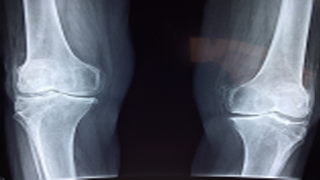

"침묵의 질병"이라고 불리는 골다공증은 뼈를 점진적으로 약화시켜 취약하게 만들고 골절되기 쉽습니다. 나이가 들수록 많은 개인, 특히 폐경기 여성은 심각한 건강상의 합병증을 유발할 수 있는 골다공증의 위험에 처하게 됩니다. 이 상태는 올바른 치료와 생활 방식의 변화를 통해 효과적으로 관리될 수 있습니다. 이 가이드에서는 뼈 건강을 지원하고 골절 위험을 줄일 수 있는 접근법에 대한 통찰력을 제공하는 것을 목표로 전문가가 권장하는 골다공증 관리 및 치료 방법을 자세히 살펴보겠습니다.

골다공증 증상, 원인 및 치료 서문 흔히 "침묵의 불만"으로 알려진 골다공증은 뼈가 점진적으로 점도를 잃고 부서지기 쉬우며 깨지기 쉬운 상태입니다. 이 진행 과정에서 지속적으로 사람들에게 영향을 미치며, 특히 폐경 후 여성에게 흔합니다. 많은 사람들이 튼튼한 뼈를 젊음과 연관시키지만, 나이가 들면서 뼈 건강을 유지하는 것은 골절을 예방하고 아이싱 이동성을 유지하는 데 필수적입니다. 뼈가 분명해지면서 약화되어 경미한 연쇄상 또는 심각한 경우 실제로 단순한 기침으로 인한 골절에 더 취약해집니다. 뼈 점도는 일반적으로 30세 전후에 최고조에 달하며 이후 점진적으로 감소합니다. 골다공증 환자의 경우 이러한 자연적인 뼈 손실 과정이 가속화됩니다. 골다공증의 위협을 증가시키는 요인으로는 노화에 따라 뼈 점도가 떨어지는 경향이 있기 때문에 연령이 주요 요인 중 하나입니다. 폐경 후 여성의 에스트로겐 감소와 유사한 호르몬 변화와 열악한 식단, 운동 부족, 과도한 음주, 흡연과 유사한 생활 요인도 중요한 원인 중 하나입니다. 골다공증의 가족력도 위협을 증가시킵니다. 골다공증의 증상과 위협 요인 골다공증의 가장 심각한 측면 중 하나는 골절이 발생하기 전까지 무증상인 경우가 많다는 것입니다. "침묵의 핀처"라고 알려진 "골조증은 고관절, 정강이증 또는 손목의 예기치 않은 골절이 발견될 때까지 눈에 띄지 않고 진행될 수 있습니다. 척추 골절은 흔하며 키의 점진적인 상실, 설계된 자세, 습관적인 역통증에 영향을 미칠 수 있습니다. 고관절 골절은 특히 심각할 수 있으며, 수술을 자주 받고 회복 시간이 길 수 있습니다. 나이, 성별, 가족력과 마찬가지로 골다공증의 일부 위협 요인은 변경할 수 없습니다. 특히 여성은 키가 작거나 체격이 작은 사람이 위험에 처해 있습니다. 하지만 조절 가능한 요인으로는 삶의 선택, 식단, 운동 등이 있습니다. 칼슘과 비타민 D가 부족한 식단은 뼈 점도에 매우 중요하기 때문에 뼈 건강 악화에 기여합니다. 또한 앉아서 생활하면 뼈가 약해질 수 있지만 걷기 및 저항 운동과 유사한 체중 부하 운동은 뼈 힘을 만들고 유지하는 데 도움이 됩니다.